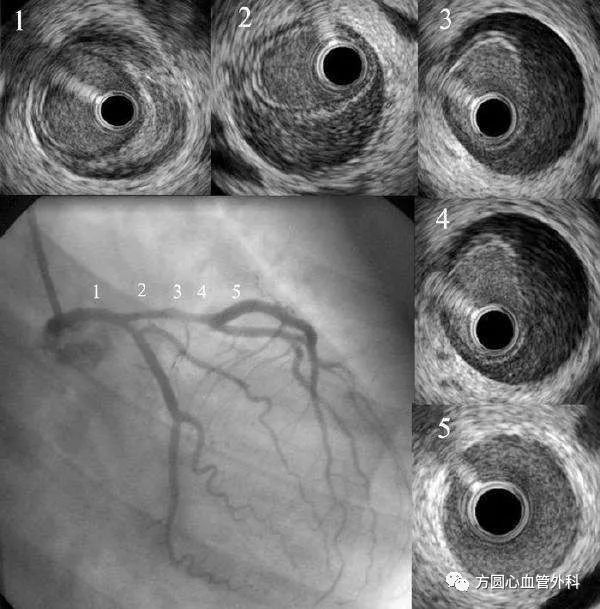

自发性冠状动脉夹层3例及诊治分析

图片尺寸700x460

自发性冠状动脉夹层致急性心肌梗死2例

图片尺寸800x805